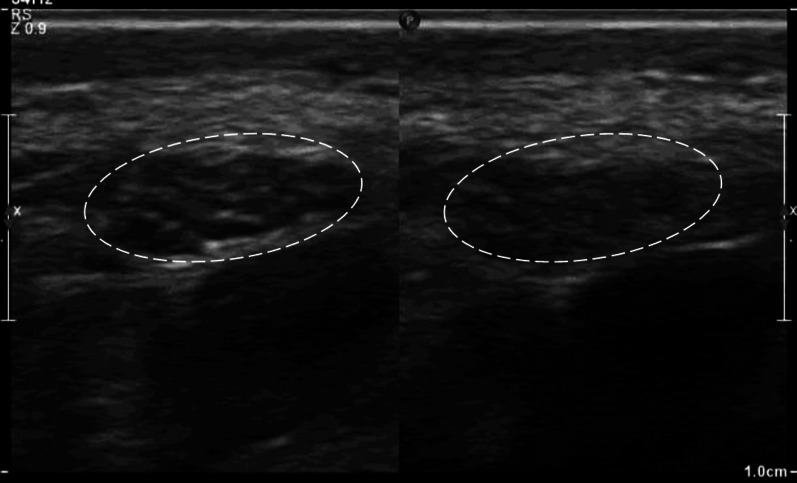

Abstract Image